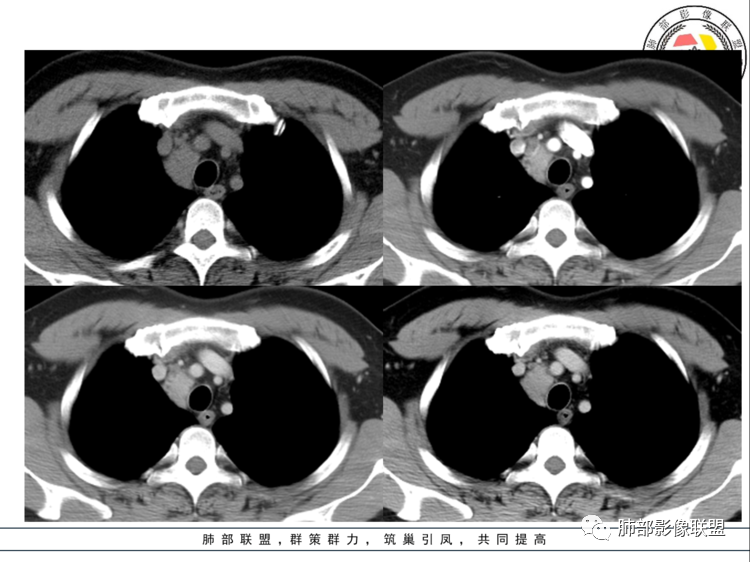

气管腔静脉间隙淋巴结增大,边界清,密度均匀,明显均匀强化,周围有小淋巴结,考虑巨淋巴结增生症。

病灶位于气管腔静脉间隙淋巴结增大,边界清,密度均匀,动脉期明显均匀强化,有小血管进入,周围有小淋巴结,考虑巨淋巴结增生症CD,鉴别诊断:神经鞘瘤

男,40岁,前纵隔类圆形肿块影,边界清晰,边缘浅分叶,病灶内密度不均,增强扫描病灶边缘呈环形强化,病灶内见坏死,考虑巨淋巴结增生,除外神经内分泌肿瘤。

右上前中纵隔占位,上腔静脉后方,血管无推移,边缘光滑,密度均匀,上下跨度较大成长条,动脉期明显强化,考虑巨淋巴结增生症CD。鉴别神经源性肿瘤,支气管囊肿。

中纵各占位,明显均匀强化,考虑透明血管型CD,鉴别副节瘤,异位甲状腺,血管瘤。

男,40岁,体检发现纵隔占位,查血常规、血生化、肿瘤标志物、尿常规大致正常。CT示纵隔占位,边缘光滑,周围可见小淋巴结影,强化动脉期明显强化,考虑CD可能

前纵隔右侧气管旁可见软组织密度肿块影,大致圆形,密度均匀,边缘清晰规整,周围脂肪间隙存在,增强明显强化。考虑良性占位,首选CD。鉴别神经源性肿瘤。

上腔静脉下方见一肿块影,边界清楚光滑,与周围组织分界清楚,平扫密度均匀,增强后均匀中度强化,强化密度略欠均匀,周围伴有淋巴结稍肿大,男性40岁,体检发现,无症状考虑CD,副节瘤(一般会有高血压),神经内分泌癌,异位胸腺瘤

前纵隔右侧气管旁可见软组织密度肿块影,密度均匀,边缘清晰规整,周围脂肪间隙存在,增强中度强化。考虑胸腺瘤。鉴别神经源性肿瘤。

气管前腔静脉后间隙类圆形肿块,密度均匀,明显强化,周围多个小淋巴结,首选CD,鉴别神经源性肿瘤

中上纵隔一欠规则软组织密度灶,边界清楚,密度均匀,周边看见散在小结节影,增强扫描动脉期明显均匀强化,静脉期延迟期造影剂缓慢减退。40岁,男性,体检发现,实验室检查正常,考虑异位甲状腺与CD、神经源性病变鉴别

前纵隔可见类圆形肿块,密度均匀,边缘光整,增强明显强化。考虑良性占位,CD首考。

中纵隔内气管右侧结节,明显强化,弱于与同层主动脉弓,静脉期强化减弱,边缘光整,考虑ct,鉴别神经源性

上中纵隔占位,边界清,均匀明显强化。疾病谱CD,神经源性肿瘤,异位甲状腺,血管源性肿瘤,副节瘤。考虑CD可能性大。

中年男性,体检,中纵隔偏右侧软组织肿块,明显强化,边界清楚,考虑巨淋巴结增生,鉴别副节瘤,胸腺瘤

中年男性,无症状,前纵隔占位,明显均匀强化,较软,考虑神经源性肿瘤,副节瘤?鉴别CD

病灶位于中纵隔,上腔静脉内后方,这里解剖主要有淋巴结,神经,血管,本例强化明显但又低于血管,周围有多枚小淋巴结,符合CD表现

上中纵隔腔静脉后气管前间隙占位,边界清,密度均匀,明显均匀强化。强化程度低于甲状腺和血管,考虑CD可能性大。

病灶边缘较光滑,密度均匀,周围脂肪间隙清楚,强化明显,周围伴多发小淋巴结,常规考虑CD,

体检发现,前中纵隔占位,位于上腔静脉后方,平扫均匀低密度,增强后明显均匀强化,边界清晰,考虑良性,CD可能大

男,40岁,体检发现纵隔占位

•查血常规、血生化、肿瘤标志物、尿常规大致正常。气管腔静脉间隙团块状影,密度均匀,边界清楚,增强扫描,明显的强化,肿块的周围气管旁见多个肿大的淋巴结,强化特点类似。考虑良性占位,巨淋巴增生症。需要与异位胸腺瘤、结节病、淋巴瘤、副神经节瘤、淋巴结转移瘤鉴别。